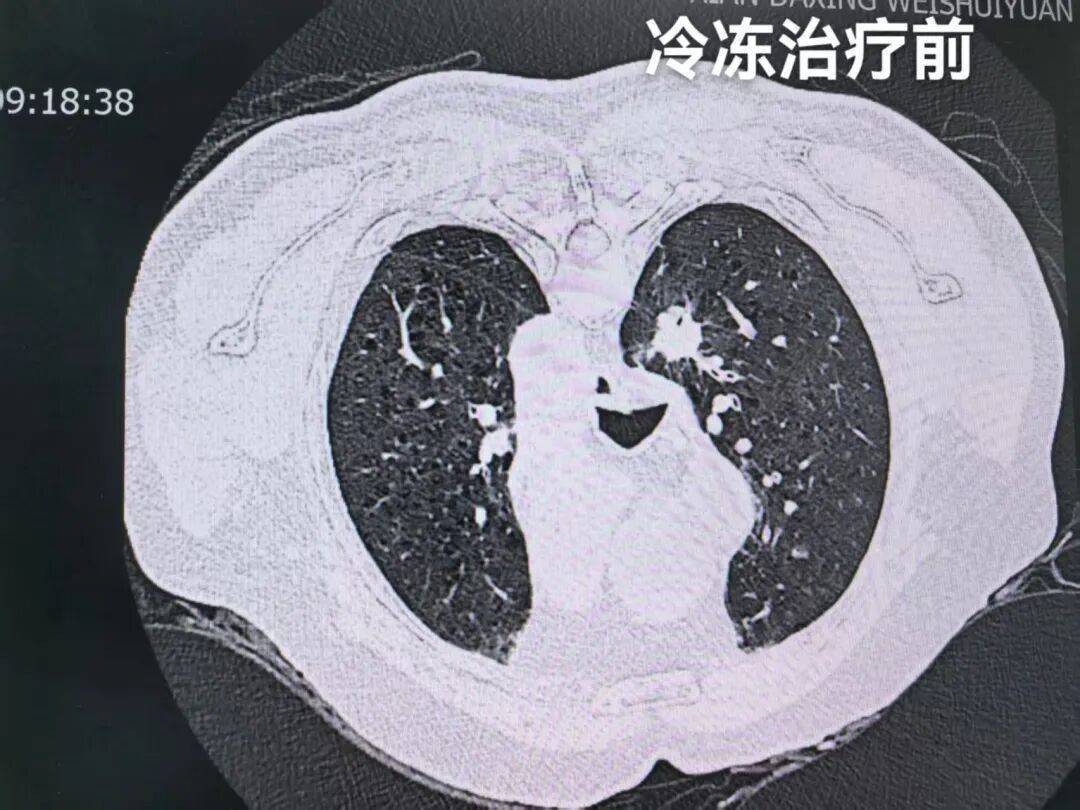

治疗流程按预设方案有序推进:第一步为CT引导精准定位,在影像科团队的协助下,医生借助CT影像系统清晰标定左肺结节的三维坐标,精准锁定病灶范围,为后续操作建立精准导航。

定位完成后,立即开展第二步穿刺活检术,医生沿定位路径实施经皮穿刺,成功获取结节组织样本后,即刻送检病理科进行快速现场评估(ROSE检测)。

这种检测能快速明确病变性质,仅耗时10分钟便出具病理报告。病理科医生随即向李大爷及家属告知结果:“确诊为非小细胞肺癌,目前病情符合冷冻治疗指征,即刻启动下一步治疗。”

第三步微创冷冻消融治疗随即开展。治疗采用三循环冷冻-复温模式:先通过冷冻针释放低温使肿瘤组织形成冰球,覆盖整个病灶区域;首次冷冻结束后进行复温,随后重复两次冷冻-复温循环,以强化对肿瘤细胞的杀伤效果。

整个治疗过程耗时约1.5小时,顺利完成。术后即时影像检查显示,肿瘤病灶已被冰球完整覆盖,消融效果达到预期。